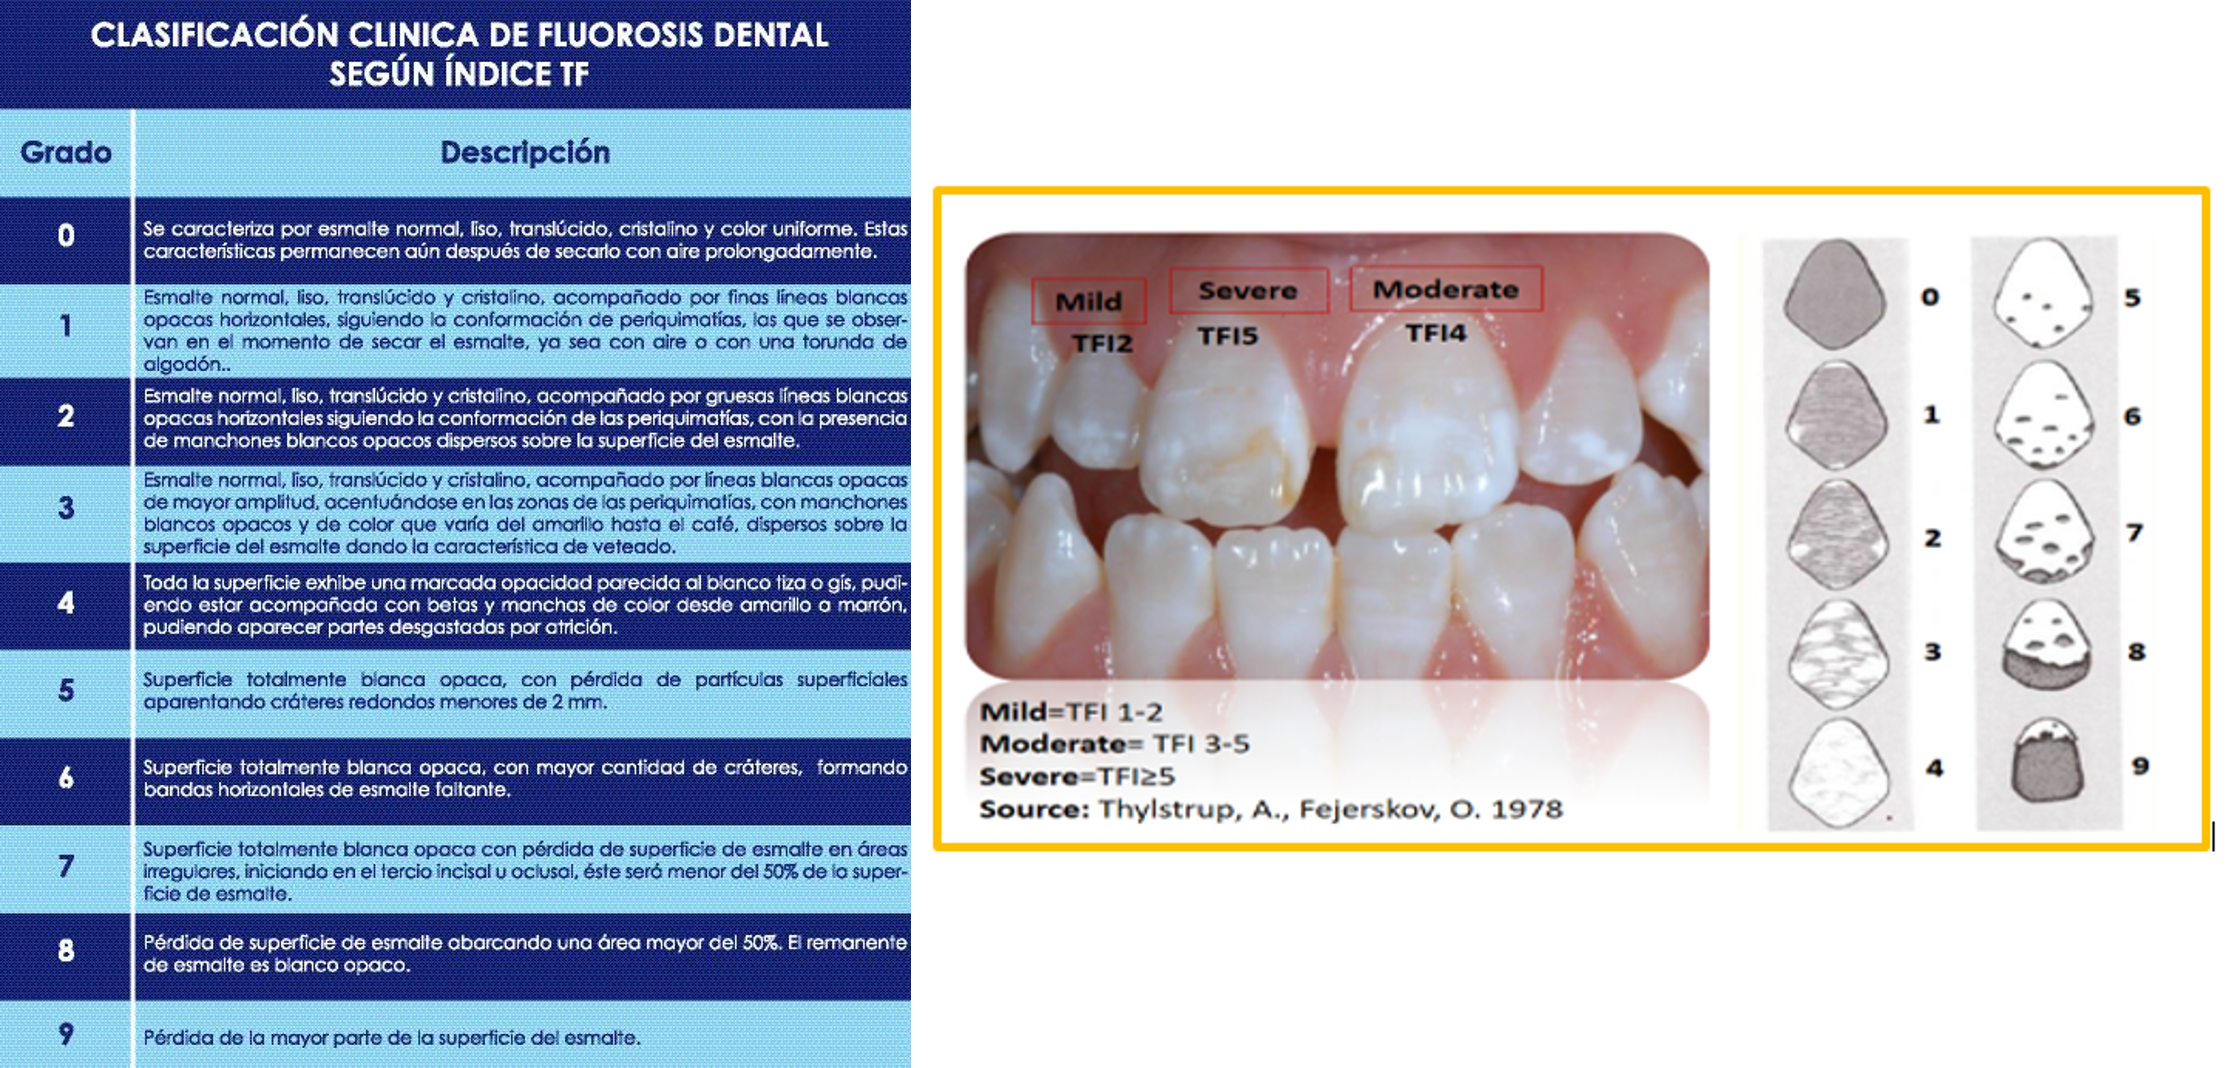

Clasificación de TFI